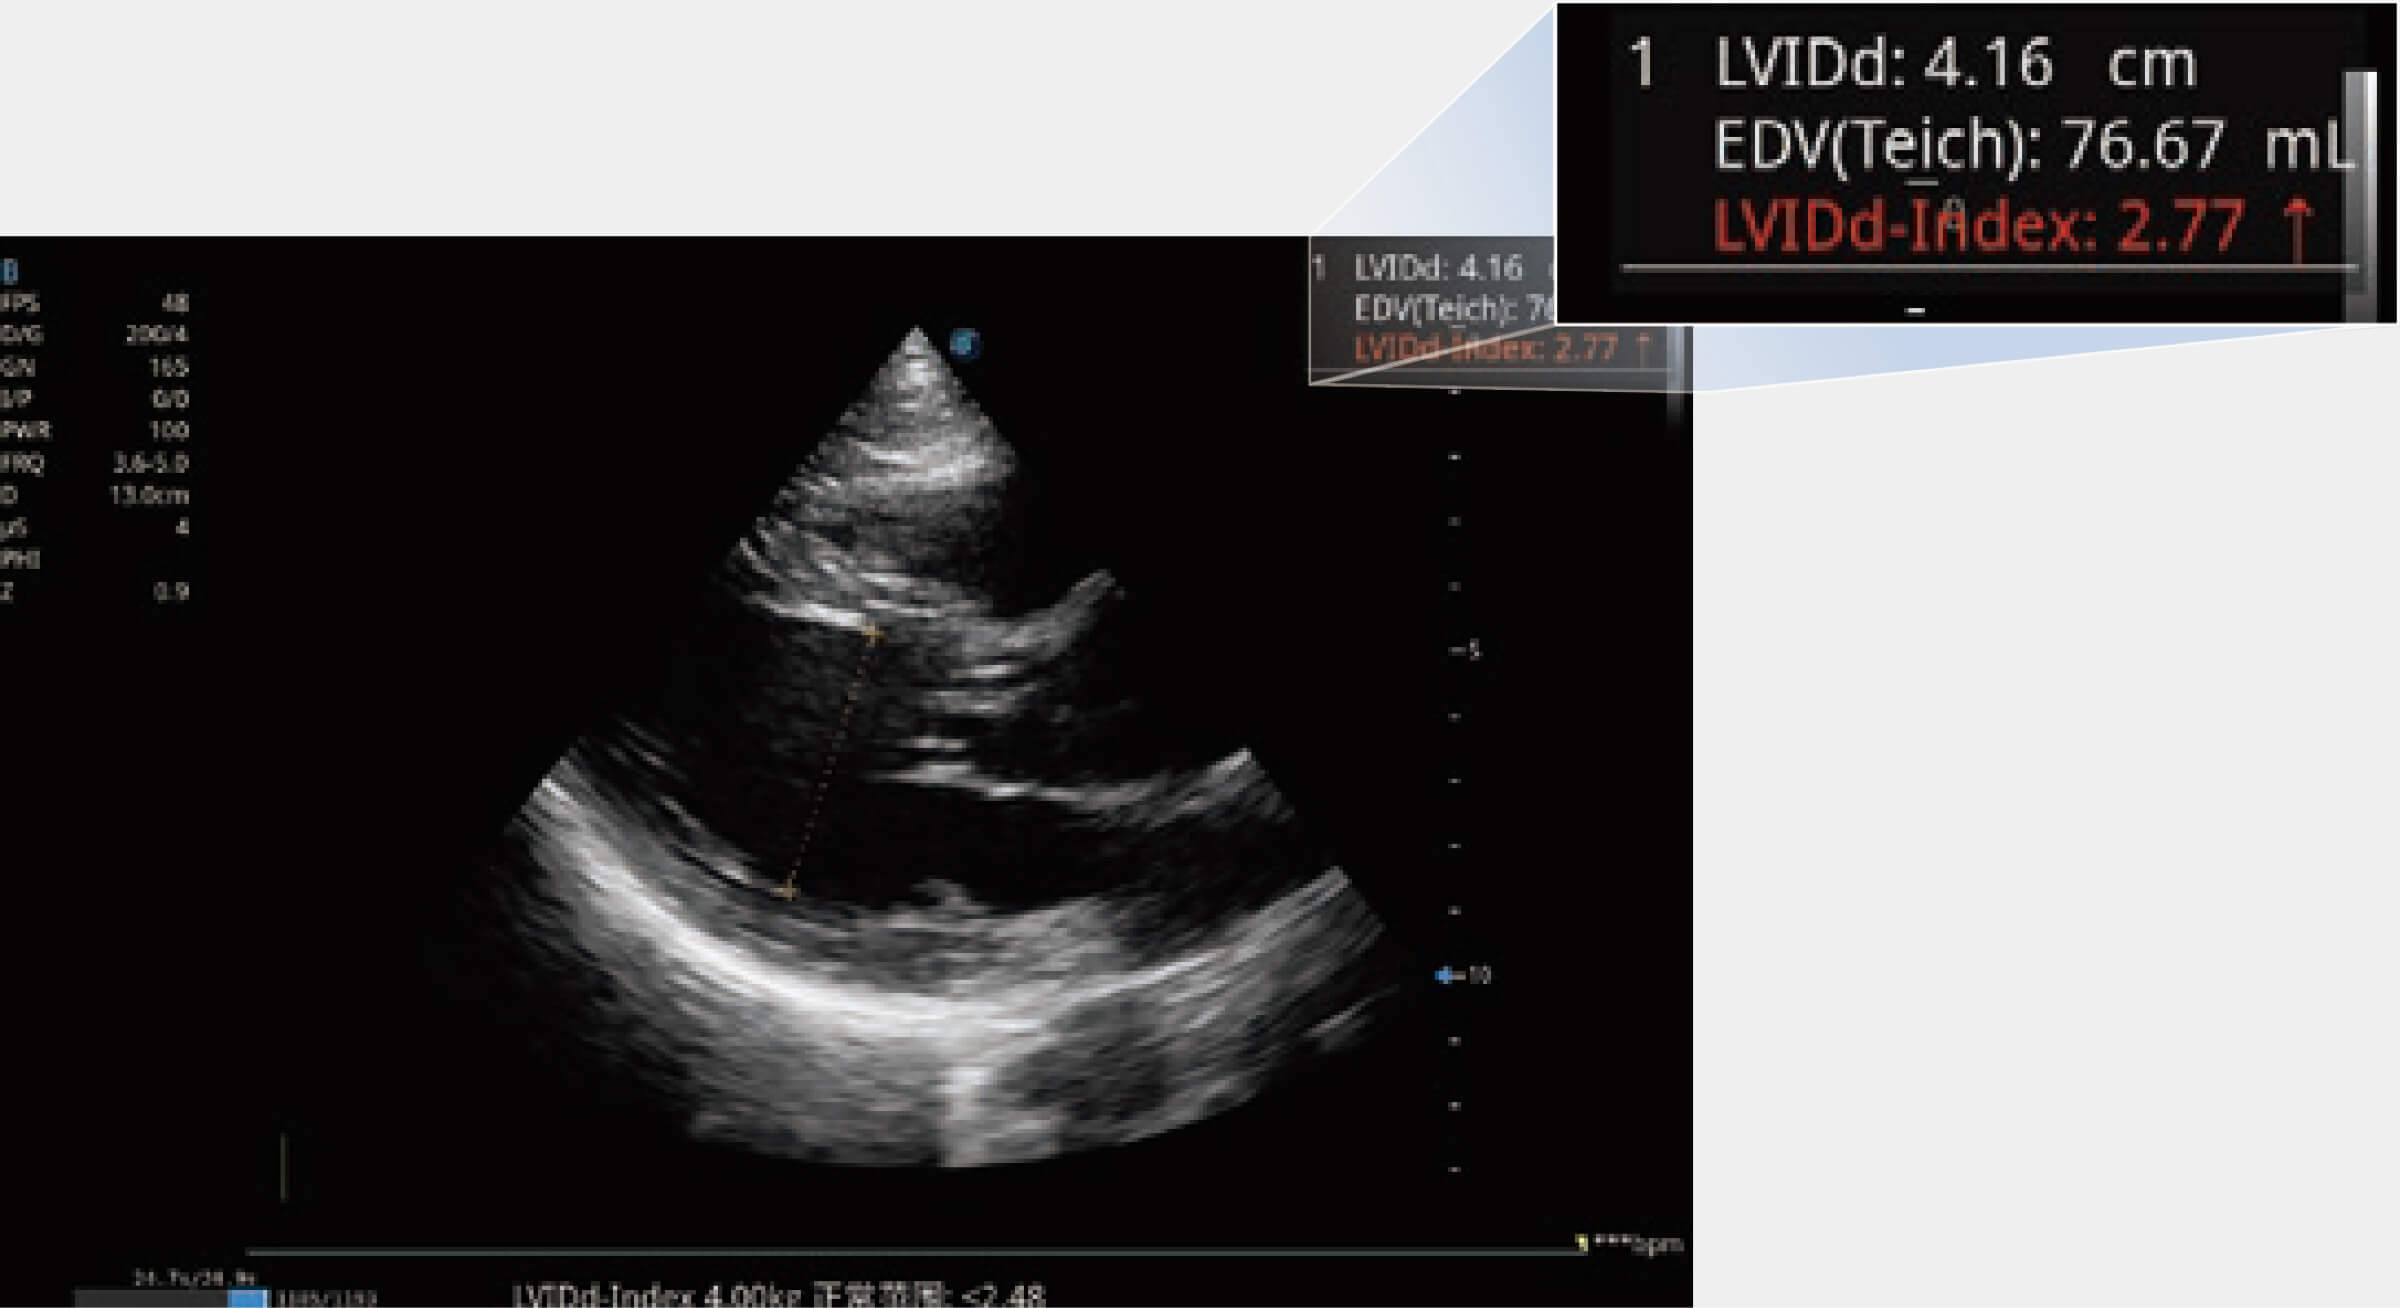

當(dāng)心臟測量結(jié)果超出正常范圍時(shí),可實(shí)時(shí)預(yù)警提示動物醫(yī)生,減少疾病漏診概率。

通過360度任意調(diào)節(jié)3條M型取樣線,在同一心動周期上觀察心臟不同位置的運(yùn)動曲線,得到準(zhǔn)確的心功能測量數(shù)據(jù),有效評估心肌運(yùn)動及左心室功能。

能夠基于左心室壁追蹤和辛普森法,自動計(jì)算射血分?jǐn)?shù),支持多個可移動點(diǎn)描跡,與手動測量相比,極大節(jié)省了動物醫(yī)生的時(shí)間和精力。